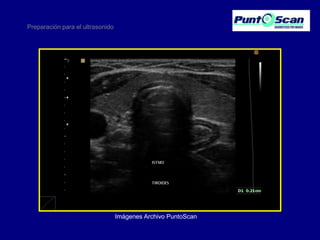

Tiroideo

Preparación para el ultrasonido

Imágenes Archivo PuntoScan

Preparación para elultrasonido • • • • • • • • • • Obstétrico tardío (12 semanas en adelante) Tiroideo Mama Testicular Transfontanelar Tejidos blandos Musculoesquelético Doppler Carotídeo Doppler venoso Doppler arterial

• 31.

Preparación para elultrasonido Imágenes Archivo PuntoScan